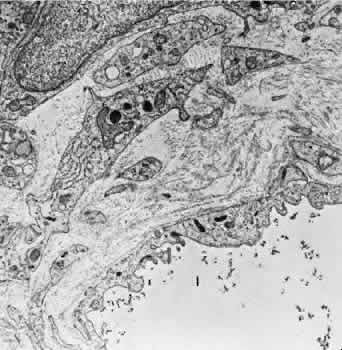

The capillaries and venules of the ciliary body are 15 to 30 μm in diameter and are fenestrated in both the pars plicata and pars plana. They closely resemble the capillaries of the choriocapillaris except that they are smaller. The fenestrae of these vessels range in size from 300 to 1,000 nm in diameter.64 The major difference between the capillaries in different areas of the ciliary body is that only those of the pars plana are in contact with the elastica of Bruch's membrane on the surface facing the pigmented epithelium. The capillaries present in the ciliary muscle are nonfenestrated (Figs. 16 and 17). The blood vessels are innervated by small branches of sympathetic fibers.

Fig. 16. Electron micrograph of a portion of a capillary facing the stroma of the ciliary process. The endothelial cell contains moderate amounts of rough-surfaced endoplasmic reticulum and numerous pinocytotic vesicles and few fenestrae. A very thin basement membrane is present. Particles of thorium dioxide may be seen in the lumen (l). This specimen was taken from a rat.

Fig. 17. Electron micrograph of a portion of a capillary from the ciliary process facing the pigmented epithelium (p). Note the absence of an elastic lamina between the vessel and the pigmented epithelium. Fenestrae are present, and the endothelium is quite attenuated. This specimen was taken from a rat injected with thorium dioxide. l, capillary lumen.